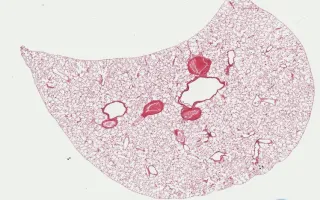

Transverse sections of large and small bronchioles.

Labels in this Slide:

- Small Bronchiole

- Ciliated Cells

- Non - Ciliated Cells

- Clara Cell

- Terminal Bronchiole